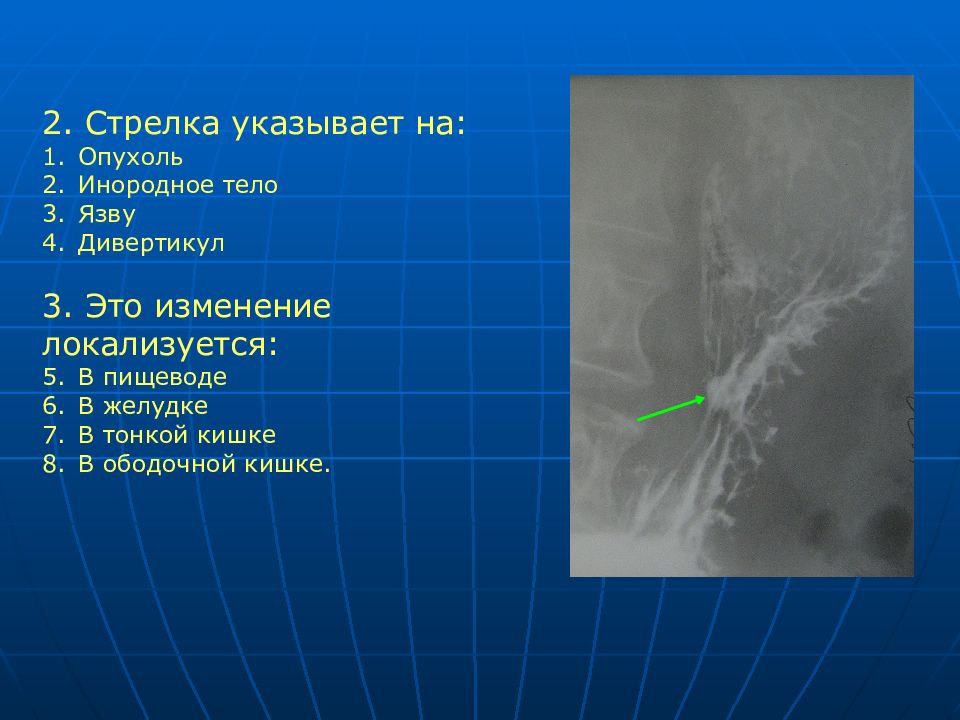

Современные технологии в медицине: рентгенодиагностика заболеваний желудка

Раздел: Фотогалерея мыслей